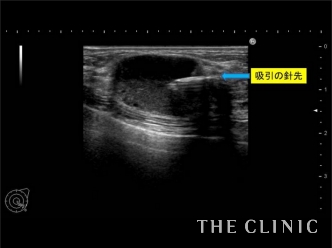

この方のしこりは吸引針で穿刺するだけの処置で除去することができるものでした。ただし、触診では確実にしこりに吸引針を刺すことが困難です。そのため、このようにリアルタイムで映し出されるエコー画像を確認しながら、しこりに吸引針を挿入し、オイルとなった脂肪を吸い出していきます。